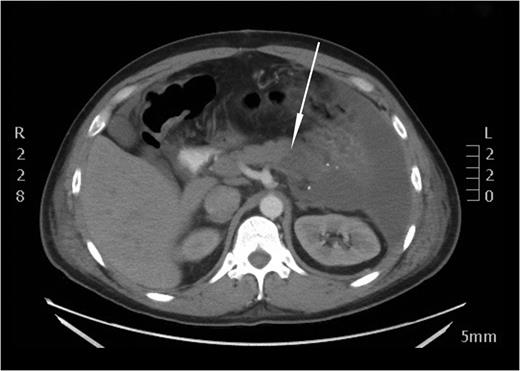

On the following day the patient experienced an intense abdominal pain, tachycardia and distress and was studied with a follow-up CT scan observing distal pancreatic ischemia (Fig. 5). As the clinical exam was consistent with peritonitis the patient was subjected to exploratory laparotomy. Similar to the CT findings, an obvious distal pancreatic ischemia was noted during surgery (Fig. 6). Distal pancreatectomy with splenectomy was performed. The pancreatic stump was oversewn and a 30 F drain was placed at the pancreatic resection margin.

An axial CT image performed on the next day after embolization. A distinct perfusion discrepancy between a normally perfused body and a non-perfused tail of the pancreas is noted (white arrow).